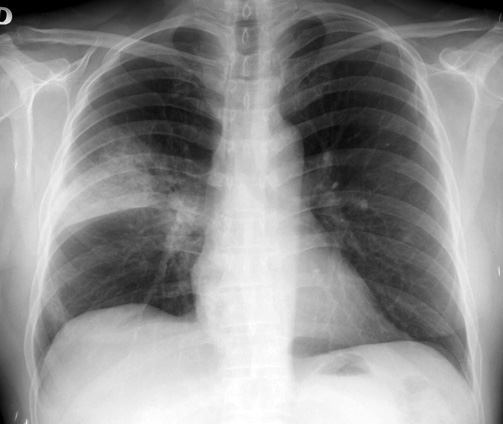

Asma en la edad adulta y adolescencia